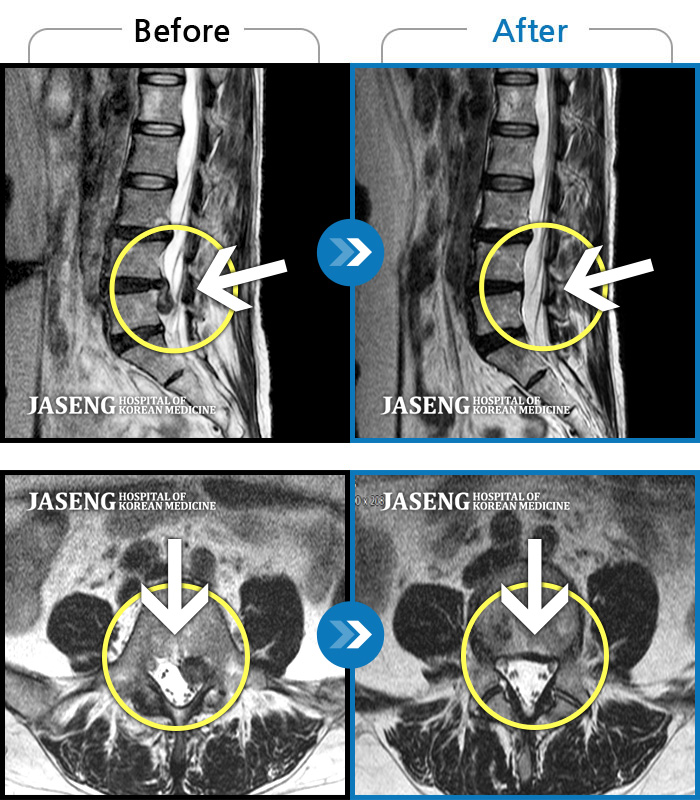

Before

After

환자에게 사전 동의를 받아 동일 조건에서 촬영되었습니다.

개인에 따라 치료 후 부작용이 발생할 수 있으니 의료진과 상담 후 치료를 진행하시기 바랍니다.

양측 허리 통증과 좌측 허벅지부터 발바닥까지 송곳으로 찌르는 듯한 통증 지속되어 내원하셨습니다.

의자 위를 여러 번 올라갔다 내려갔다 반복한 뒤 극심한 하요부 통증 및 좌측 하지부 저림